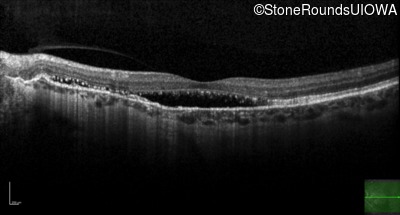

Pseudoxanthoma Elasticum (IID2)

Age at visit: 58 years

Diagnosis & molecular findings

Disease Gene Allele 1 variant(s) Allele 2 variant(s) Inheritance mode

Pseudoxanthoma Elasticum ABCC6 Gly928 del4tacGGCA IVS21+1 G>T AR